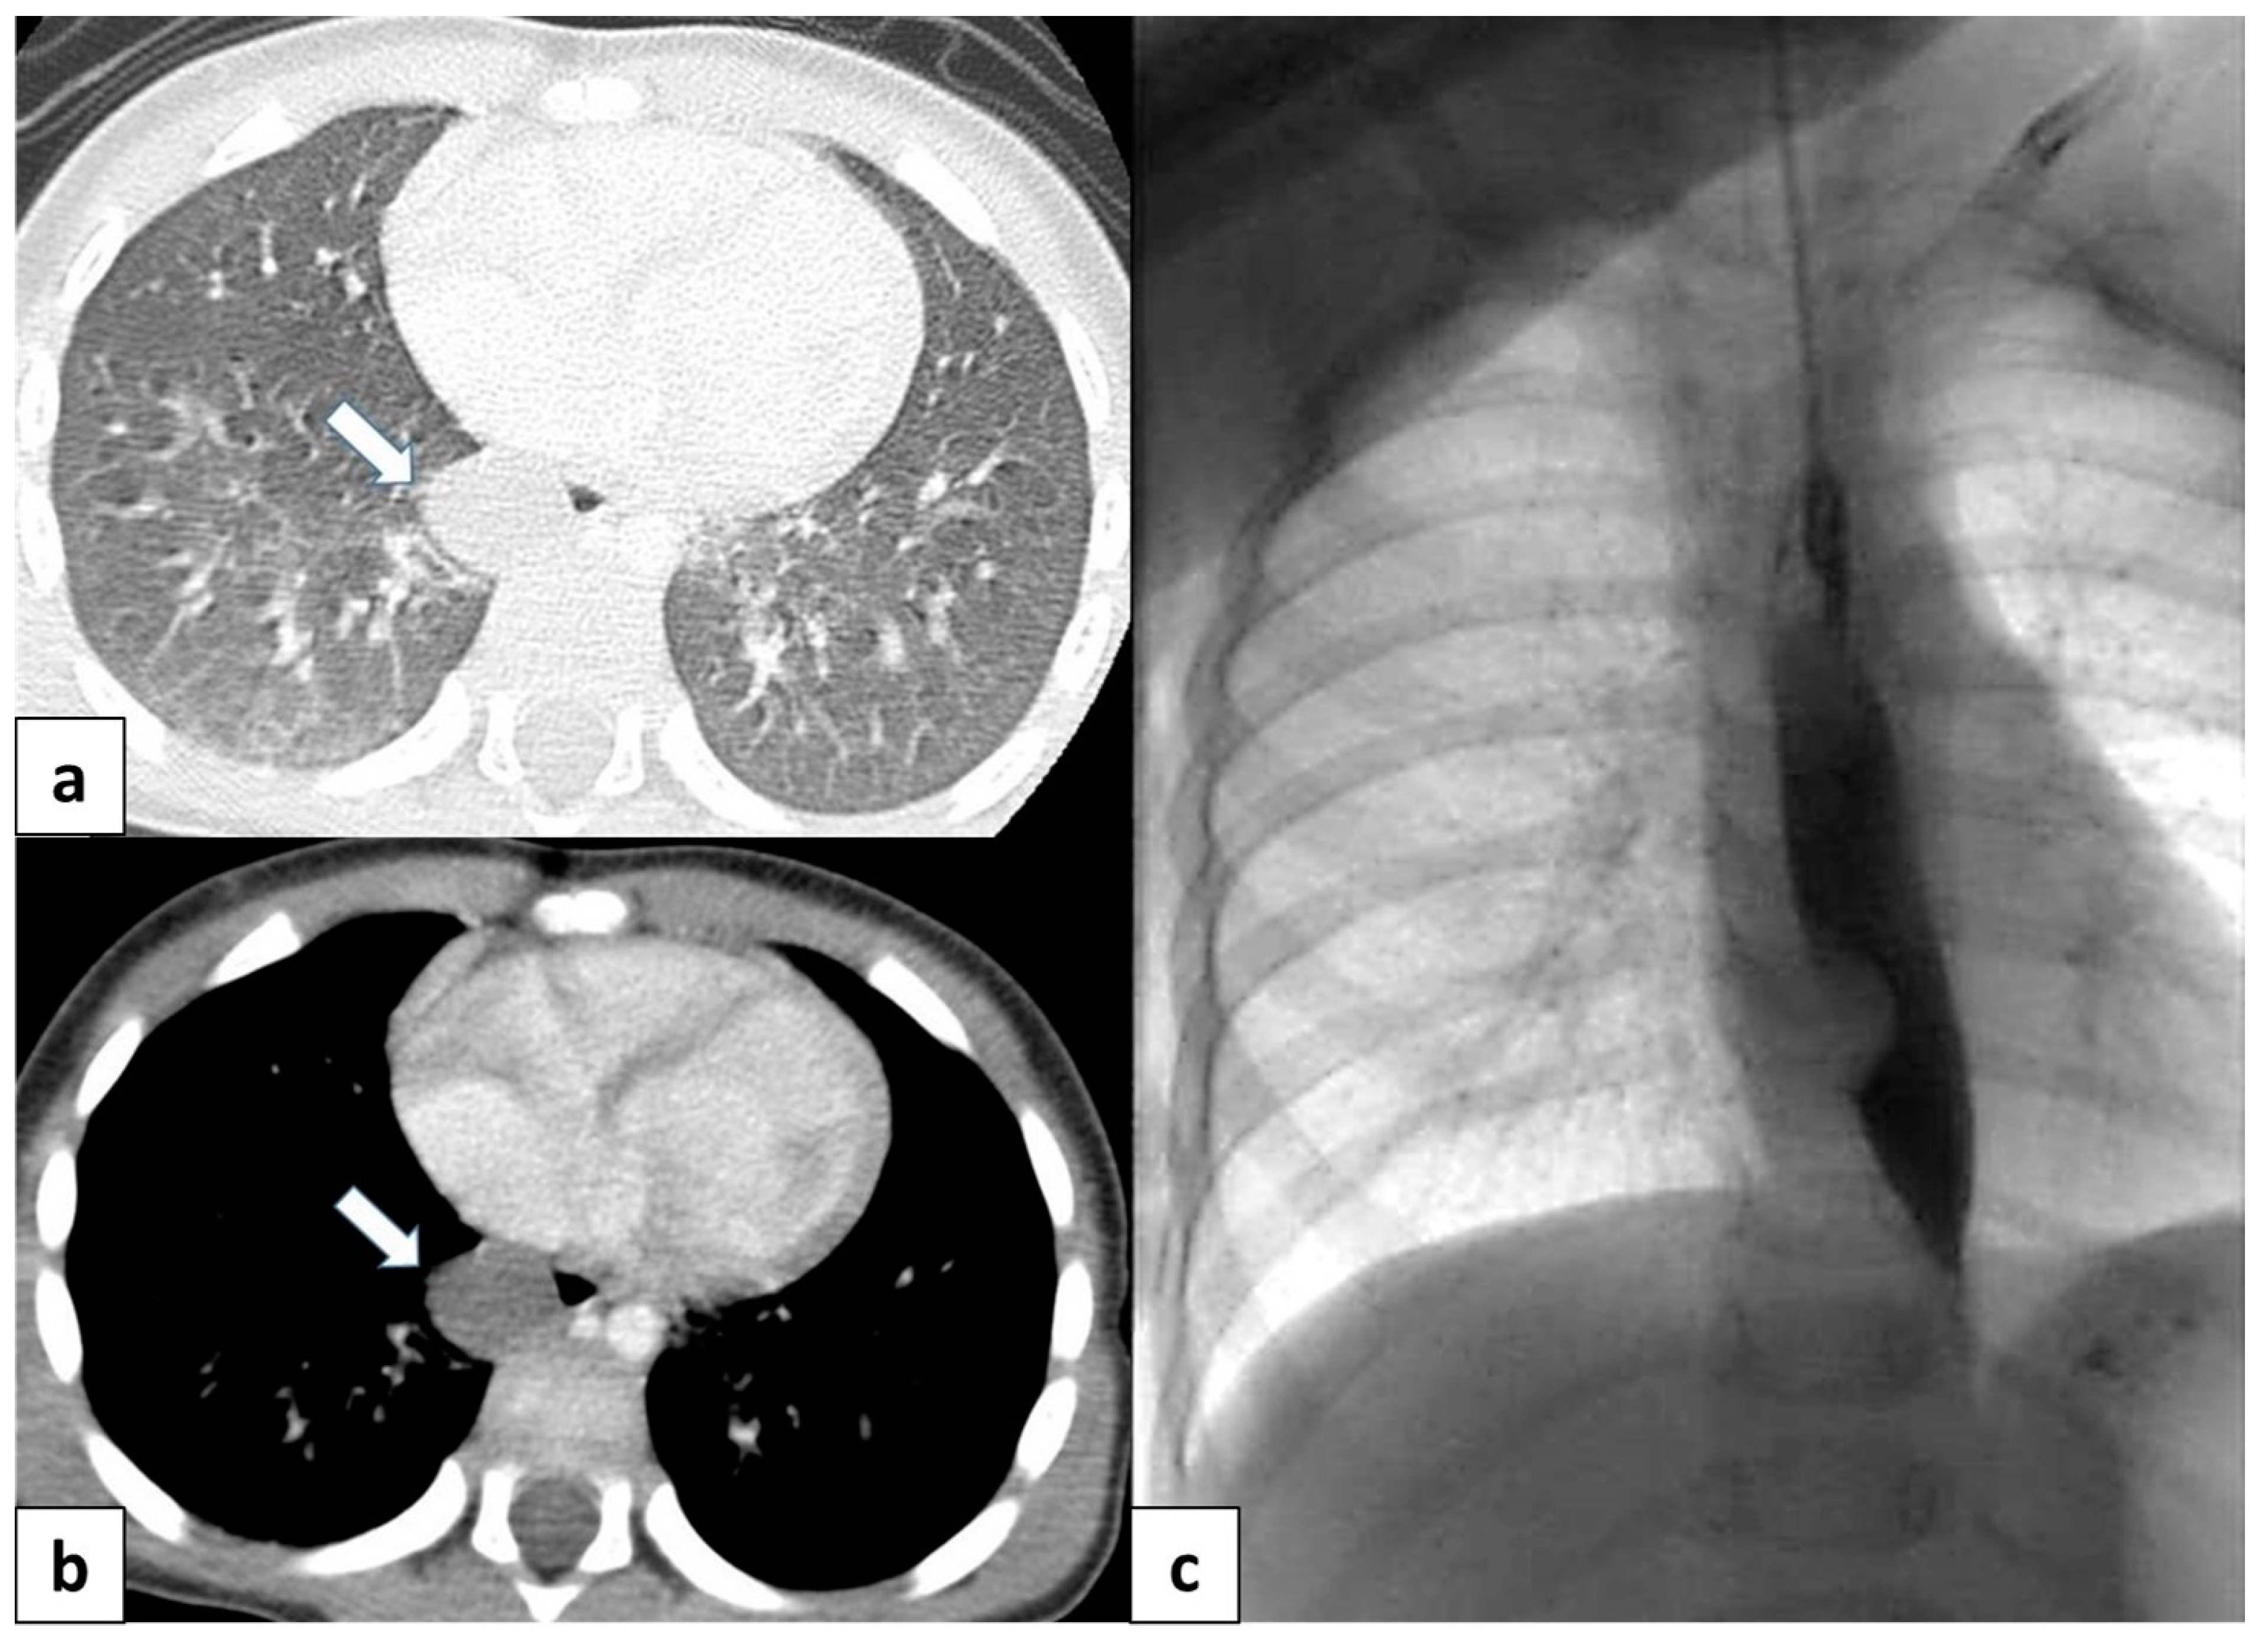

3.6.1. Pulmonary Sequestration

| Intralobar Type | Extralobar Type | |

|---|---|---|

| Incidence | 75% | 25% |

| Cause | acquired or congenital | congenital |

| Timing of Diagnosis | childhood or adulthood | Prenatal–neonatal period |

| Pleural Investment | within lobe without its own pleura | with its own lung pleura |

| Arterial Supply | thoracic or abdominal aorta | abdominal aorta |

| Venous Drainage | pulmonary venous system | systemic venous system |

| Association with Other Congenital Anomalies | rare | common |